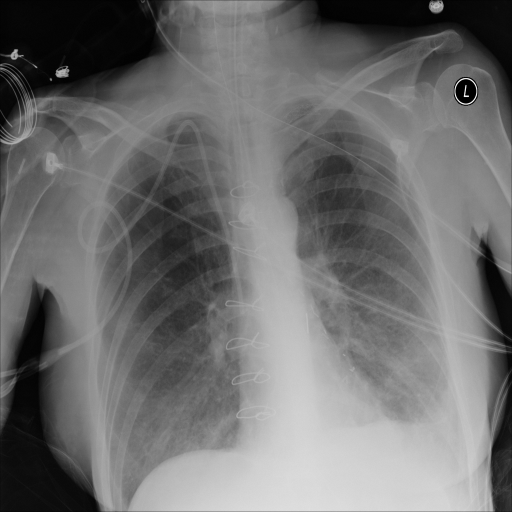

Refer to caption

(a) Original

case 1

(b) ϵ=103HWitalic-ϵsuperscript103𝐻𝑊\epsilon=10^{3}\cdot H\cdot W

(c) ϵ=102HWitalic-ϵsuperscript102𝐻𝑊\epsilon=10^{2}\cdot H\cdot W

(d) ϵ=101HWitalic-ϵsuperscript101𝐻𝑊\epsilon=10^{1}\cdot H\cdot W

(e) Original

case 2

(f) ϵ=103HWitalic-ϵsuperscript103𝐻𝑊\epsilon=10^{3}\cdot H\cdot W

(g) ϵ=102HWitalic-ϵsuperscript102𝐻𝑊\epsilon=10^{2}\cdot H\cdot W

(h) ϵ=101HWitalic-ϵsuperscript101𝐻𝑊\epsilon=10^{1}\cdot H\cdot W

(i) Original

case 3

(j) ϵ=103HWitalic-ϵsuperscript103𝐻𝑊\epsilon=10^{3}\cdot H\cdot W

(k) ϵ=102HWitalic-ϵsuperscript102𝐻𝑊\epsilon=10^{2}\cdot H\cdot W

(l) ϵ=101HWitalic-ϵsuperscript101𝐻𝑊\epsilon=10^{1}\cdot H\cdot W

(m) Original

case 4

(n) ϵ=103HWitalic-ϵsuperscript103𝐻𝑊\epsilon=10^{3}\cdot H\cdot W

(o) ϵ=102HWitalic-ϵsuperscript102𝐻𝑊\epsilon=10^{2}\cdot H\cdot W

(p) ϵ=101HWitalic-ϵsuperscript101𝐻𝑊\epsilon=10^{1}\cdot H\cdot W

Figure 2: ϵitalic-ϵ\epsilon-LDP-processed CXR images obtained with DP-GLOW.

In Fig. 1, we show four ϵitalic-ϵ\epsilon-LDP-processed CXR images of clinical cases obtained with the image domain LDP, which directly imposes the Laplace mechanism on the input image, with different privacy budgets together with the original images. Fig. 2 shows four ϵitalic-ϵ\epsilon-LDP-processed CXR images of clinical cases obtained with DP-GLOW and different privacy budgets together with the original images. In case 1 for DP-GLOW, there is decreased permeability in the bilateral hilar regions. Although this hilar opacity tends to be preserved with a larger privacy budget, the entire image is degraded when the privacy budget becomes 101HWsuperscript101𝐻𝑊10^{1}\cdot H\cdot W. A similar tendency is observed in the images of all the four cases for DP-GLOW; for example, in case 4 with ϵ=101HWitalic-ϵsuperscript101𝐻𝑊\epsilon=10^{1}\cdot H\cdot W, the lung opacity suggesting pneumonia in the right lower lung field is well preserved, while the entire image is degraded.